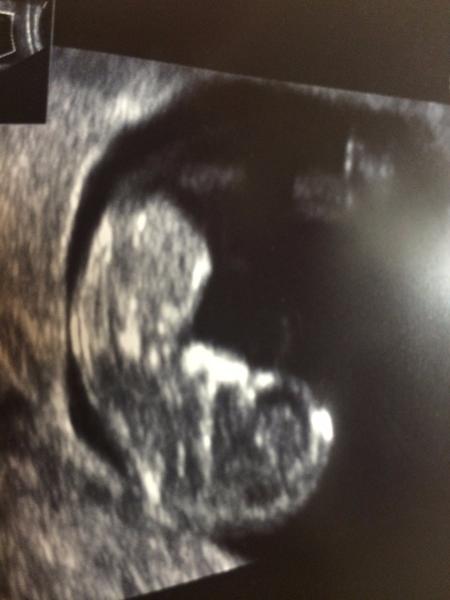

@moje135 Jo, fakt to tak je. Špatný pocit hoď za hlavu a už se tím netrap, nejsi první ani poslední, kdo v kocovince ujel. Užívej těhotenství a vědomí, že otec je ten, kterého za otce chceš. Pro ještě větší klid posílám foto naší začátkosrpnové "výroby". Váček jsem viděla už 25.8. Teď by to jako tečku nezobrazil snad už ani prototyp ultrazvuku z roku 1946. Foto je z 5. 10. 🙂

Tvoje oplodnění je zákonitě novějšího data 🙂.